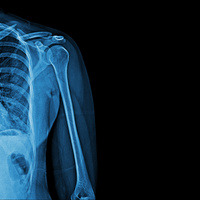

- X-rays (Radiographs): The most common imaging tool in orthopedics, X-rays help visualize bones and joint alignment, detect fractures, arthritis, and other bone abnormalities.

- The imaging services performed at our office include X-rays and Ultrasounds.